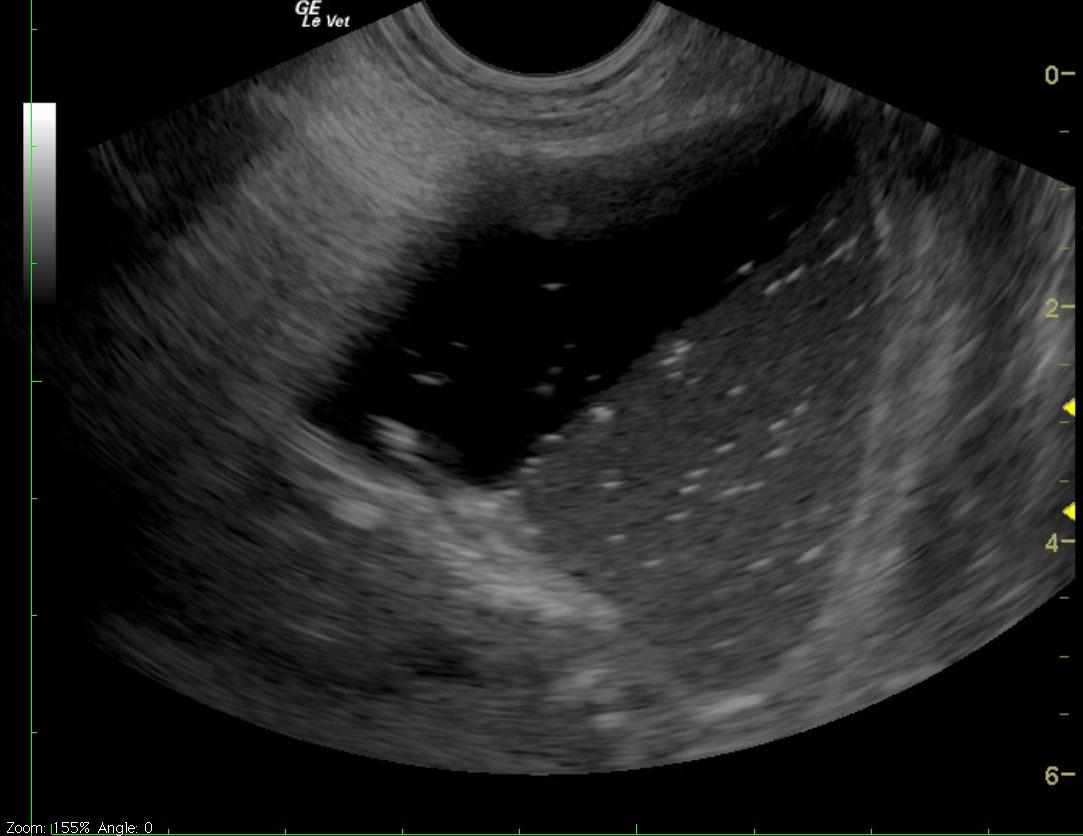

Ultrasound reveals marked gastric distention with fluid, dependent echogenic contents and a small amount of gas. Complete loss of gastric peristalsis appears to be present. Mild-to-moderate fluid distention of the proximal small intestines is also apparent. The proximal small bowel walls are thickened and hypoechoic with subtle loss of distinction between layers. The affected small intestines appear to be bordered by mildly echogenic mesenteric fat.